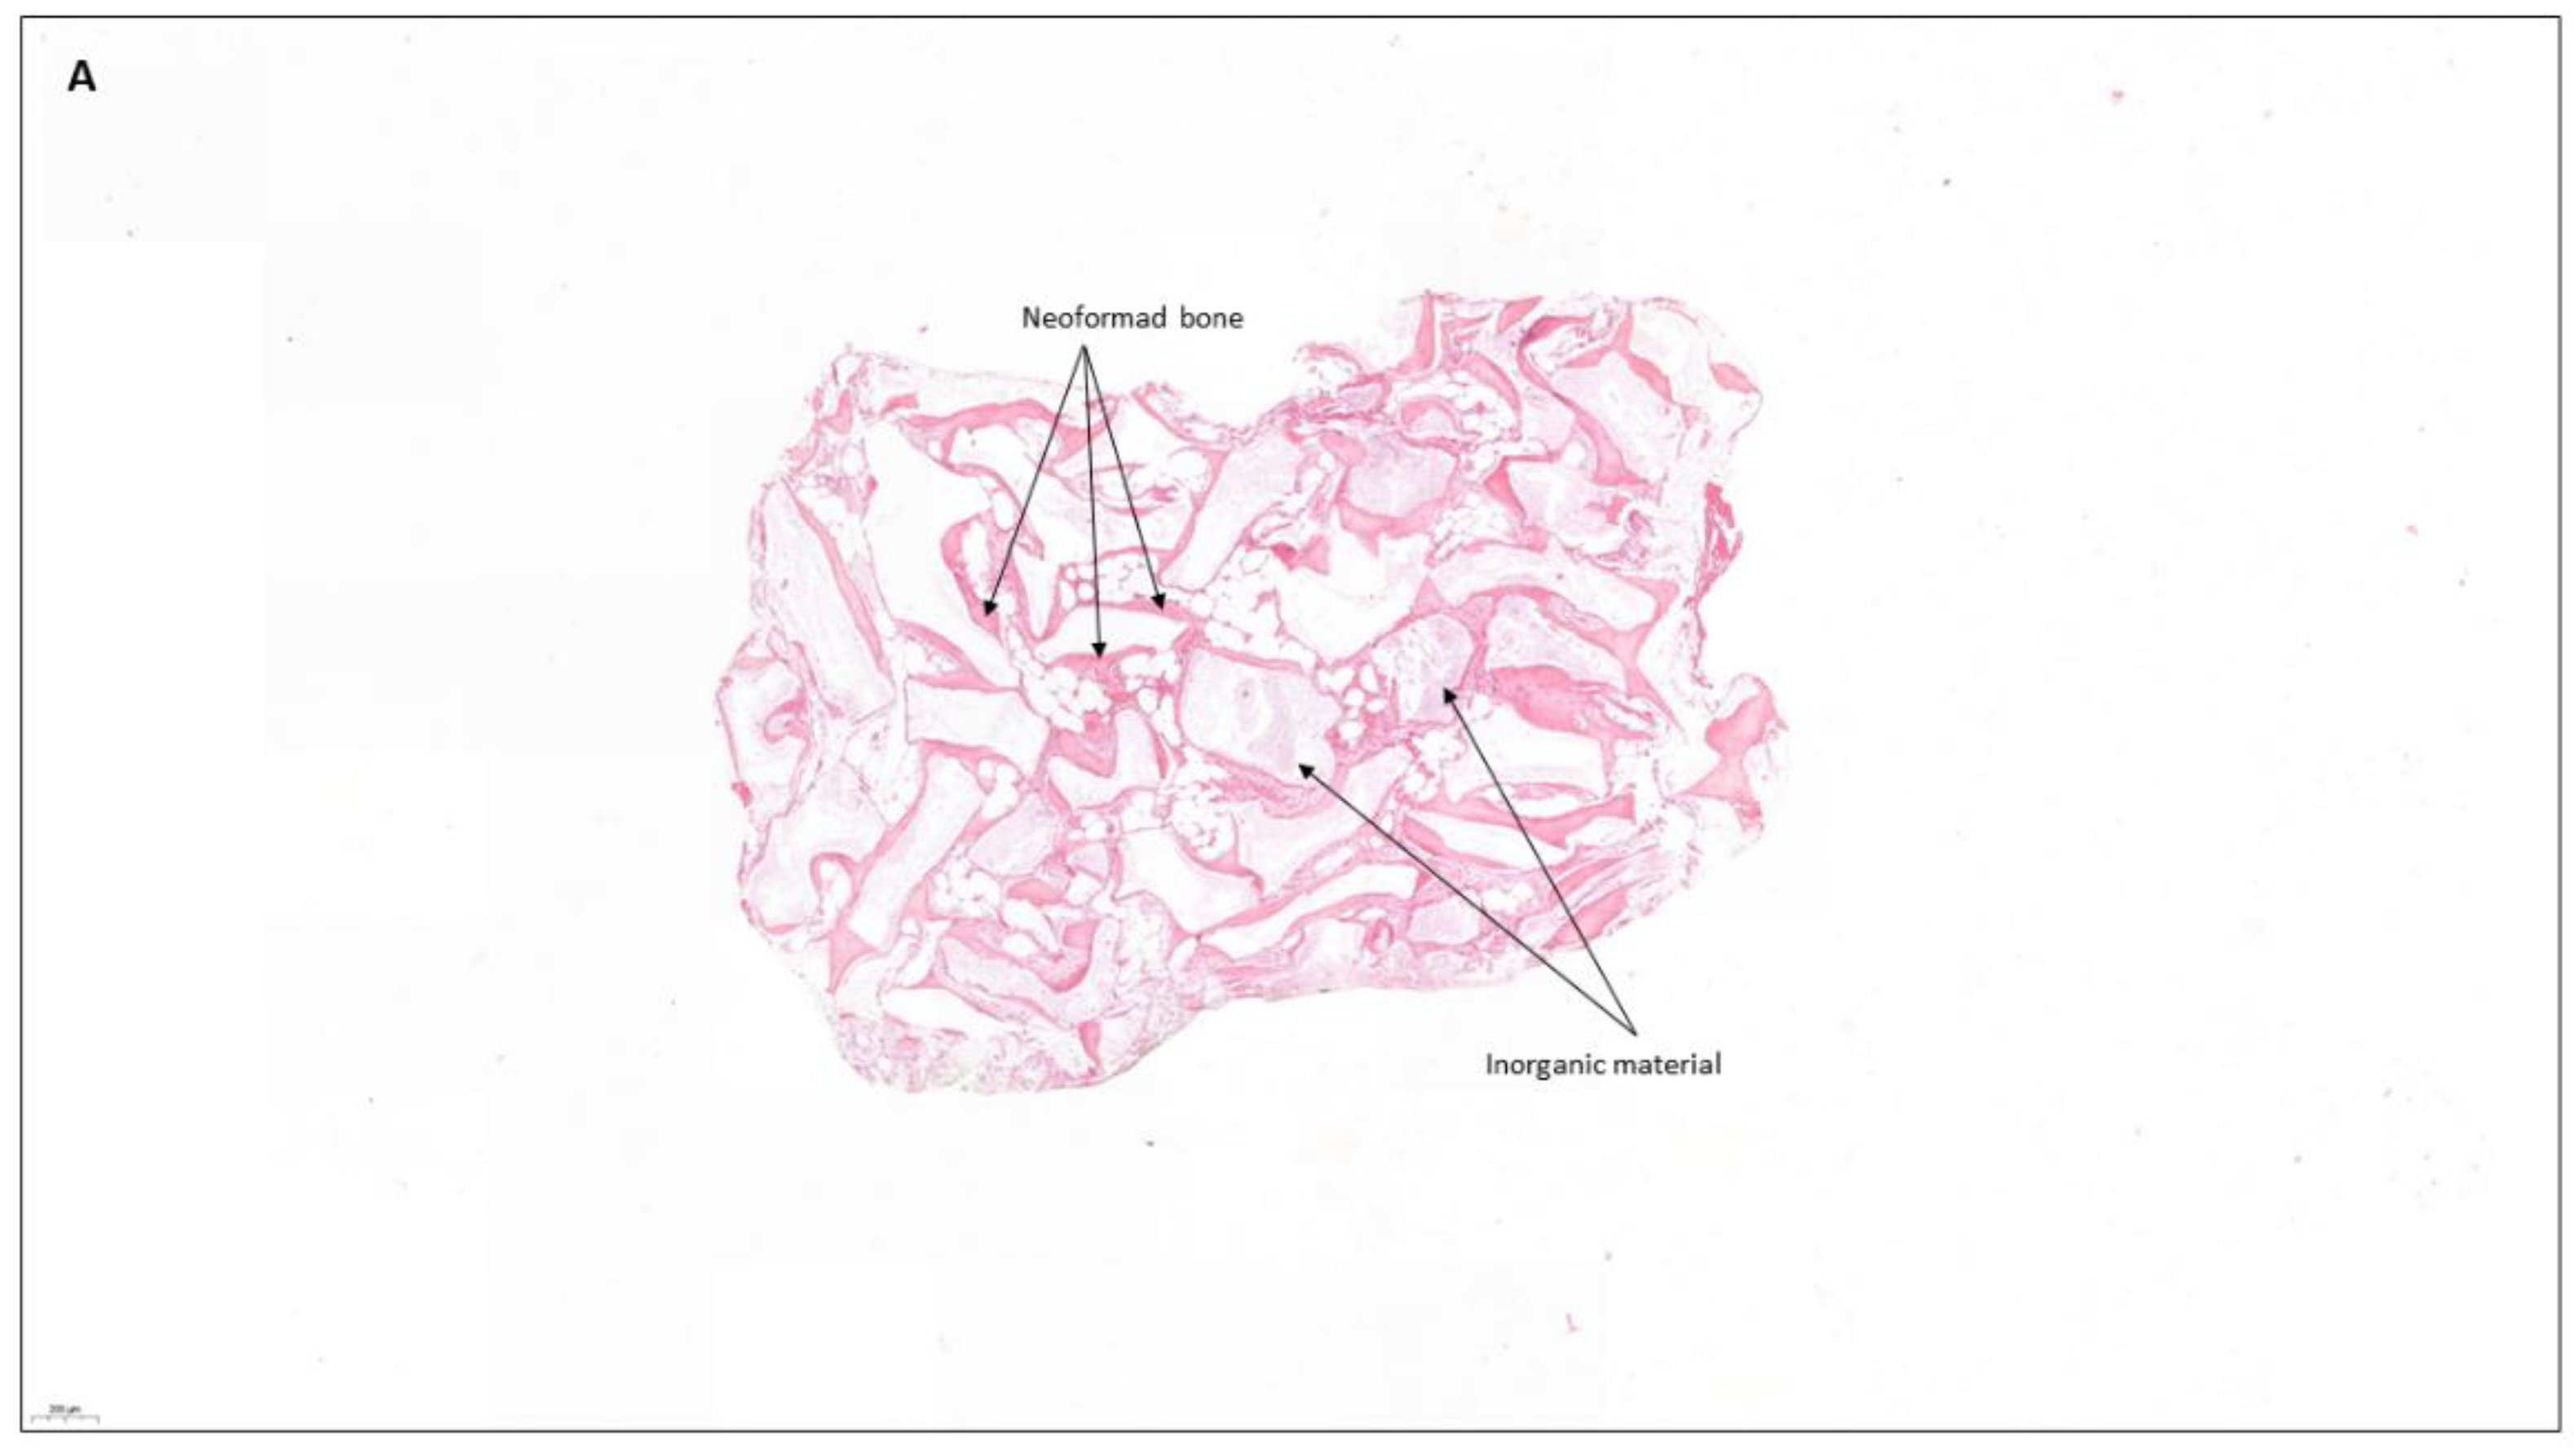

| Machtei et al. [30] 2018 RCT | n: 11 7M/4F 45–80 = 64 years old | To compare the dimensional changes and bone quality of calcium sulfate (BCS/HA) and bovine xenograft (BDX) in socket preservation cases. | At 4 months Bone height loss: BDX 0.25 mm, BCS/HA 0.65 mm, Control 1.7 mmBone width loss at −3 mm: BDX 1.56 ± 0.4 mm, BCS/HA 0.5 ± 0.4 mm Control 2.96 ± 0.3 mmNew bone formation: BDX 21,5%, BCS/HA 44.4% y Control 81,5%. Remaining graft material: BDX 44.18%, BCS/HA 16.51%. | Calcium sulfate can be used as the material of choice for socket preservation with similar and sometimes even better results than bovine xenograft. | |